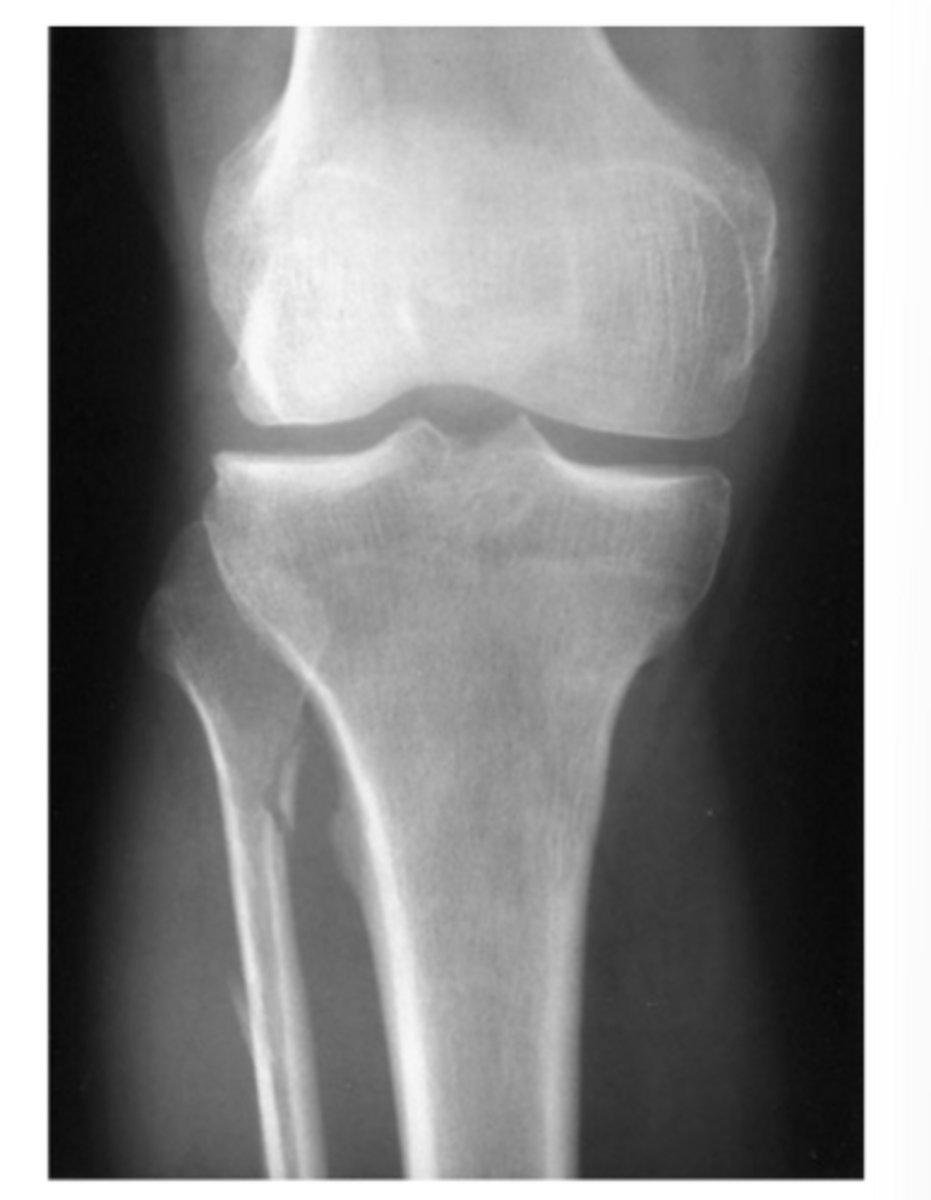

A 15-year-old boy complains of ankle pain after a fall (AP and lateral views of the ankle).

What is the abnormality in Case 6-5 (Figure 6-12)?

Answer

D.

Note how the lucencies rule vertically through the epiphysis and obliquely through the metaphysis. This is also called a Salter Harris IV fracture